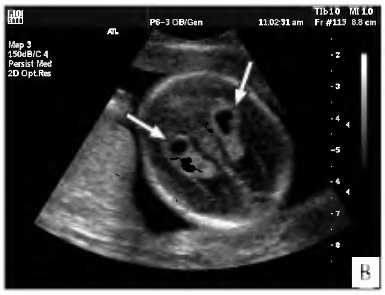

[7], [8], [9], [10], [11], [12]

ΠΠΈΡΡΡ ΡΠΎΡΡΠ΄ΠΈΡΡΡΡ ΡΠΏΠ»Π΅ΡΠ΅Π½ΠΈΠΉ Ρ ΠΏΠ»ΠΎΠ΄Π°

Π‘ΠΎΡΡΠ΄ΠΈΡΡΡΠ΅ ΡΠΏΠ»Π΅ΡΠ΅Π½ΠΈΡ β ΡΠ²Π»ΡΡΡΡΡ ΠΏΠ΅ΡΠ²ΠΎΠΉ ΡΠΈΡΡΠ΅ΠΌΠΎΠΉ ΠΎΡΠ³Π°Π½ΠΈΠ·ΠΌΠ°, ΠΊΠΎΡΠΎΡΠ°Ρ Π½Π°ΡΠΈΠ½Π°Π΅Ρ ΡΠ°Π·Π²ΠΈΠ²Π°ΡΡΡΡ ΡΠΆΠ΅ Π½Π° ΡΠ΅ΡΡΠΎΠΉ Π½Π΅Π΄Π΅Π»Π΅ ΠΏΠΎΡΠ»Π΅ Π·Π°ΡΠ°ΡΠΈΡ. Π ΡΠΎΡΡΠ΄ΠΈΡΡΡΡ ΡΠΏΠ»Π΅ΡΠ΅Π½ΠΈΡΡ Π½Π΅Ρ Π½Π΅ΡΠ²Π½ΡΡ ΠΊΠ»Π΅ΡΠΎΠΊ, Π½ΠΎ ΠΎΠ½ΠΈ ΠΈΠ³ΡΠ°ΡΡ Π²Π°ΠΆΠ½ΡΡ ΡΠΎΠ»Ρ Π² Π΄Π°Π»ΡΠ½Π΅ΠΉΡΠ΅ΠΌ ΠΎΠ±ΡΠ°Π·ΠΎΠ²Π°Π½ΠΈΠΈ Π½Π΅ΡΠ²Π½ΡΡ ΠΊΠ»Π΅ΡΠΎΠΊ ΠΌΠΎΠ·Π³Π°. ΠΡΠΎ Π΄ΠΎΡΡΠ°ΡΠΎΡΠ½ΠΎ ΡΠ»ΠΎΠΆΠ½ΡΠ΅ ΠΎΠ±ΡΠ°Π·ΠΎΠ²Π°Π½ΠΈΡ ΠΈ Π½Π°Π»ΠΈΡΠΈΠ΅ Π΄Π²ΡΡ ΡΠΎΡΡΠ΄ΠΈΡΡΡΡ ΡΠΏΠ»Π΅ΡΠ΅Π½ΠΈΠΉ Π³ΠΎΠ²ΠΎΡΠΈΡ ΠΎ ΡΠΎΠΌ, ΡΡΠΎ Π² Π΄Π°Π»ΡΠ½Π΅ΠΉΡΠ΅ΠΌ Π΄Π²Π΅ ΠΏΠΎΠ»ΠΎΠ²ΠΈΠ½Ρ ΠΌΠΎΠ·Π³Π° Π±ΡΠ΄ΡΡ Π°Π΄Π΅ΠΊΠ²Π°ΡΠ½ΠΎ ΡΠ°Π·Π²ΠΈΠ²Π°ΡΡΡΡ. ΠΠΈΡΡΡ ΡΠΎΡΡΠ΄ΠΈΡΡΡΡ ΡΠΏΠ»Π΅ΡΠ΅Π½ΠΈΠΉ Ρ ΠΏΠ»ΠΎΠ΄Π° β ΡΡΠΎ ΠΊΡΡΠ³Π»ΡΠ΅ ΠΏΠΎΠ»ΠΎΡΡΠΈ, Π·Π°ΠΏΠΎΠ»Π½Π΅Π½Π½ΡΠ΅ ΠΆΠΈΠ΄ΠΊΠΎΡΡΡΡ, ΡΠ°ΡΠΏΠΎΠ»ΠΎΠΆΠ΅Π½Π½ΡΠ΅ Π² ΠΎΠ±Π»Π°ΡΡΠΈ ΠΌΠΎΠ·Π³Π° Π² ΡΠ°ΠΉΠΎΠ½Π΅ ΡΠΎΡΡΠ΄ΠΈΡΡΡΡ ΡΠΏΠ»Π΅ΡΠ΅Π½ΠΈΠΉ. Π’Π°ΠΊΠΈΠ΅ ΠΎΠ±ΡΠ°Π·ΠΎΠ²Π°Π½ΠΈΡ ΡΠ°ΡΠ΅ Π²ΡΠ΅Π³ΠΎ ΠΎΠ±Π½Π°ΡΡΠΆΠΈΠ²Π°ΡΡΡΡ Ρ ΠΏΠ»ΠΎΠ΄Π° Π² ΠΏΠ΅ΡΠΈΠΎΠ΄Π΅ ΠΌΠ΅ΠΆΠ΄Ρ 14ΠΉ ΠΈ 22ΠΉ Π½Π΅Π΄Π΅Π»ΡΠΌΠΈ. Π‘ΡΠ°ΡΠΈΡΡΠΈΠΊΠ° ΠΏΠΎΠΊΠ°Π·ΡΠ²Π°Π΅Ρ, ΡΡΠΎ ΡΠΆΠ΅ ΠΊ 28ΠΉ Π½Π΅Π΄Π΅Π»Π΅ ΠΊΠΈΡΡΡ ΠΏΠΎΡΡΠ΅ΠΏΠ΅Π½Π½ΠΎ ΡΠ°ΠΌΠΎΡΠ°ΡΡΠ°ΡΡΠ²Π°ΡΡΡΡ ΠΈ ΠΈΡΡΠ΅Π·Π°ΡΡ, ΡΠ°ΠΊ ΠΊΠ°ΠΊ ΠΊ ΡΡΠΎΠΌΡ Π²ΡΠ΅ΠΌΠ΅Π½ΠΈ ΡΠΆΠ΅ Π½Π°ΡΠΈΠ½Π°Π΅Ρ ΡΠ²ΠΎΡ ΡΠ°Π·Π²ΠΈΠ²Π°ΡΠΈΠ΅ ΠΌΠΎΠ·Π³ ΡΠ΅Π±ΡΠ½ΠΊΠ° ΠΈ Π΅Π³ΠΎ ΡΡΠ½ΠΊΡΠΈΠΎΠ½Π°Π»ΡΠ½ΡΠ΅ ΠΏΠΎΠΊΠ°Π·Π°ΡΠ΅Π»ΠΈ ΡΡΠ°Π±ΠΈΠ»ΠΈΠ·ΠΈΡΡΡΡΡΡ. ΠΠ° ΡΠ΅Π³ΠΎΠ΄Π½ΡΡΠ½ΠΈΠΉ Π΄Π΅Π½Ρ ΠΊΠΈΡΡΡ ΡΠΎΡΡΠ΄ΠΈΡΡΡΡ ΡΠΏΠ»Π΅ΡΠ΅Π½ΠΈΠΉ Ρ ΠΏΠ»ΠΎΠ΄Π° Π² ΠΌΠ΅Π΄ΠΈΡΠΈΠ½ΡΠΊΠΎΠΌ ΠΌΠΈΡΠ΅ ΠΎΡΠ½ΠΎΡΡΡ ΠΊ Β«ΠΌΡΠ³ΠΊΠΈΠΌ ΠΌΠ°ΡΠΊΠ΅ΡΠ°ΠΌΒ». ΠΡΠΎ ΠΏΠ°ΡΠΎΠ»ΠΎΠ³ΠΈΠΈ, ΠΏΡΠΈ ΠΎΡΠ΄Π΅Π»ΡΠ½ΠΎΠΌ ΡΠ°ΡΡΠΌΠΎΡΡΠ΅Π½ΠΈΠΈ Π°Π±ΡΠΎΠ»ΡΡΠ½ΠΎ Π±Π΅Π·Π²ΡΠ΅Π΄Π½Ρ ΠΈ Π½Π΅ Π²Π»ΠΈΡΡΡ Π½Π° ΡΡΠ½ΠΊΡΠΈΠΈ ΠΎΡΠ³Π°Π½ΠΈΠ·ΠΌΠ°, Π½ΠΎ ΠΌΠΎΠ³ΡΡ Π±ΡΡΡ ΡΠ²ΡΠ·Π°Π½Ρ Ρ ΠΏΠΎΠ²ΡΡΠ΅Π½ΠΈΠ΅ΠΌ Π²ΠΎΠ·ΠΌΠΎΠΆΠ½ΠΎΡΡΠΈ ΡΠ°Π·Π²ΠΈΡΠΈΡ Π΄ΡΡΠ³ΠΈΡ Π·Π°Π±ΠΎΠ»Π΅Π²Π°Π½ΠΈΠΉ ΠΈΠ»ΠΈ Π½Π°ΡΡΡΠ΅Π½ΠΈΠΉ ΡΡΠ½ΠΊΡΠΈΠΎΠ½Π°Π»ΡΠ½ΡΡ ΡΠΈΡΡΠ΅ΠΌ ΠΎΡΠ³Π°Π½ΠΈΠ·ΠΌΠ°. ΠΠΈΡΡΡ ΡΠΎΡΡΠ΄ΠΈΡΡΡΡ ΡΠΏΠ»Π΅ΡΠ΅Π½ΠΈΠΉ ΡΠΎΠ²Π΅ΡΡΠ΅Π½Π½ΠΎ Π½Π΅ ΠΈΠΌΠ΅ΡΡ Π²Π»ΠΈΡΠ½ΠΈΡ Π½Π° ΡΠ°Π·Π²ΠΈΡΠΈΠ΅ ΠΏΠ»ΠΎΠ΄Π° ΠΈ Π΅Π³ΠΎ ΡΠ°ΠΌΠΎΡΡΠ²ΡΡΠ²ΠΈΠ΅. ΠΠ½ΠΎΠ³ΠΈΠ΅ ΠΌΠ°ΡΠ΅ΡΠΈ ΠΏΡΠΎΡΠ²Π»ΡΡΡ ΠΈΠ·Π»ΠΈΡΠ½Π΅Π΅ Π±Π΅ΡΠΏΠΎΠΊΠΎΠΉΡΡΠ²ΠΎ, Π΅ΡΠ»ΠΈ Π£ΠΠ ΠΏΠΎΠΊΠ°Π·ΡΠ²Π°Π΅Ρ ΠΏΡΠΈΡΡΡΡΡΠ²ΠΈΠ΅ ΠΊΠΈΡΡ ΡΠΎΡΡΠ΄ΠΈΡΡΡΡ ΡΠΏΠ»Π΅ΡΠ΅Π½ΠΈΠΉ Ρ ΠΏΠ»ΠΎΠ΄Π°, Π½ΠΎ ΠΊΠ²Π°Π»ΠΈΡΠΈΡΠΈΡΠΎΠ²Π°Π½Π½ΡΠ΅ Π²ΡΠ°ΡΠΈ ΡΠ°Π·ΡΡΡΠ½ΡΡΡ, ΡΡΠΎ ΡΡΠΎ Π½Π΅ ΡΡΡΠ°ΡΠ½ΠΎ ΠΈ Π½Π΅Ρ ΠΏΠΎΠ²ΠΎΠ΄ΠΎΠ² Π΄Π»Ρ Π±Π΅ΡΠΏΠΎΠΊΠΎΠΉΡΡΠ²Π°.